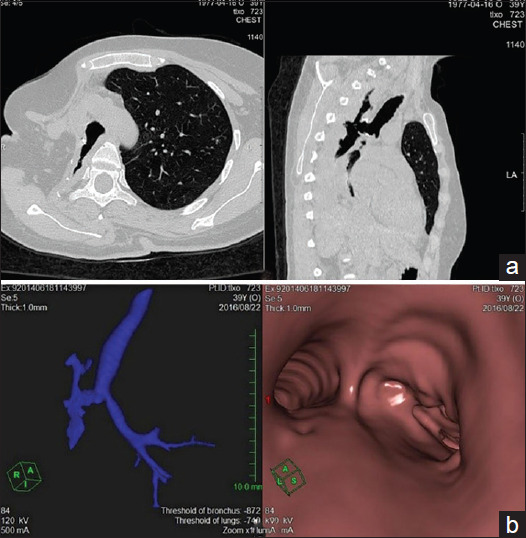

A 39-year-old female has postoperative empyema with bronchial stump fistula (BSF) after pneumonectomy due to ineffective tuberculosis chemotherapy. Transpleural reamputation of the right main bronchial stump with simultaneous 8-rib thoracoplasty, 6 attempts at endobronchial valve implantation and thoracostomy have failed to cure BSF and empyema. Consequently, an alternative treatment-transsternal transpericardial wedge-shaped resection of the tracheal bifurcation was performed despite its difficulty and was successful. This clinical case demonstrates the complications of BSF with tuberculosis empyema treatment in spite of there existing many alternative therapies. The need for new more effective treatments is highlighted, as well as safe and less technically difficult interventions which could assist patients with BSF.

Abstract Image